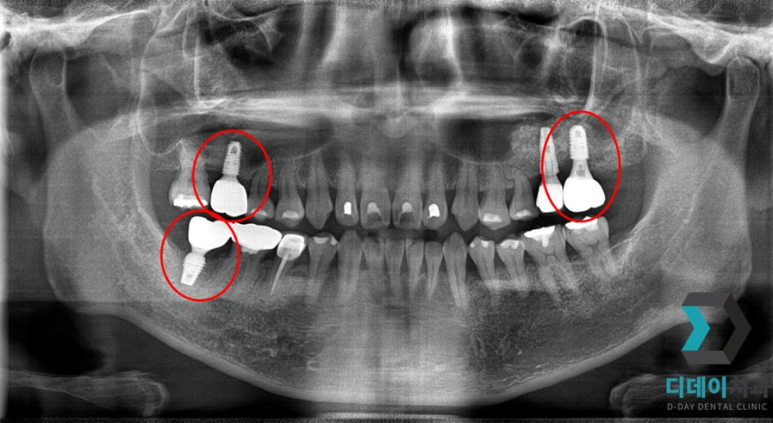

<전 2022-02-23>

<후 2022-10-14>